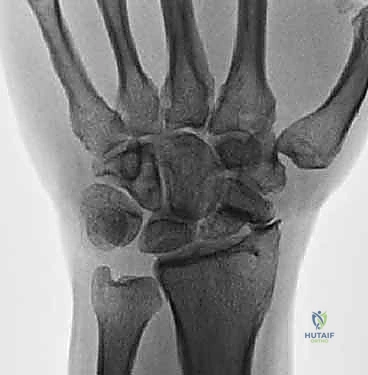

- الأشعة السينية الرقمية (Digital X-rays): بأوضاع متعددة (AP, Lateral, Scaphoid view) لتقييم زوايا العظام ودرجة الانهيار.

- الأشعة المقطعية (CT Scan): وهي المعيار الذهبي لتقييم حجم العظم المتآكل بدقة ثلاثية الأبعاد، وتحديد مدى الخشونة في المفاصل المحيطة.